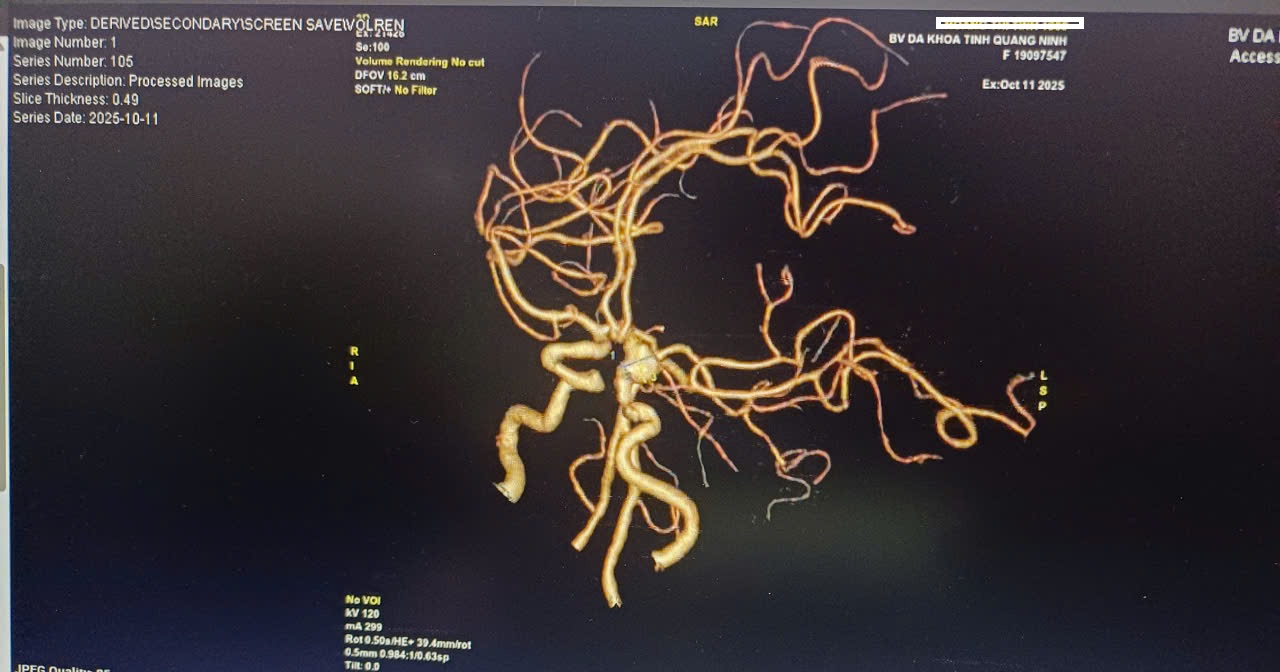

Sau khi thăm khám, bệnh nhân được xử trí hạ huyết áp khẩn cấp, thực hiện các xét nghiệm và chụp CT sọ não cấp cứu. Kết quả cho thấy xuất huyết dưới nhện hai bán cầu và quanh các bể não - não thất, được chẩn đoán xuất huyết não do tăng huyết áp.

Bệnh nhân được kiểm soát huyết áp tích cực, chống phù não và chuyển tuyến lên Bệnh viện Đa khoa tỉnh Quảng Ninh để tiếp tục điều trị chuyên sâu. Tại đây, bệnh nhân được chẩn đoán: Xuất huyết dưới nhện do vỡ phình động mạch cảnh trong trái - Tăng huyết áp. Được tiến hành mổ cấp cứu, kẹp tạo hình động mạch cảnh trong trái; sau mổ bệnh nhân được điều trị hồi sức tích cực (HSTC), thở máy, theo dõi sát huyết áp, hiện tình trạng đã tỉnh táo và đang hồi phục tốt.